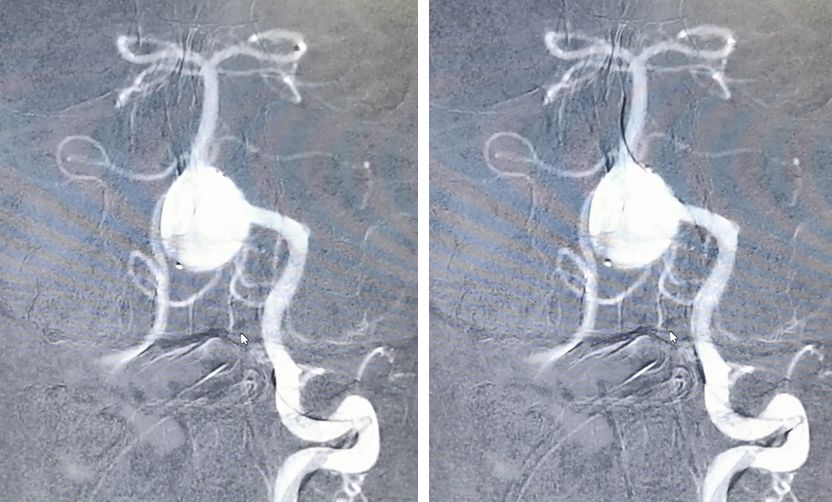

左椎动脉造影显示椎-基底动脉及远端血管通畅,动脉瘤虽然部分显影,但是PED最终会让动脉瘤完全修复。

结局:

患者术后各项体征稳定,无特殊不适。两天后出院。